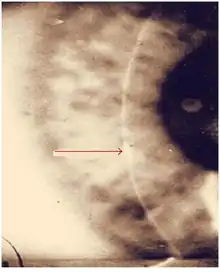

| Interstitial keratitis in congenital syphilis | |

Interstitial keratitis (IK) is corneal scarring due to chronic inflammation of the corneal stroma.[1] Interstitial means space between cells i.e. corneal stroma which lies between the epithelium and the endothelium. Keratitis means corneal inflammation.

Acutely, early symptoms include a painful, photophobic, red watery eye. This is due to active corneal inflammation resulting in vascular invasion and stromal necrosis which can be diffuse or localized. This causes the pinkish discoloration of what was a clear transparent normal corneal tissue (called Salmon patch of Hutchinson).

Such vascularization is likely to result in blurring of vision secondary to corneal stromal scarring, the presence of ghost vessels, and thinning of the cornea, especially if it involves the visual axis.

The corneal scarring is the end result of the initial invasion of blood vessels into the corneal stroma as part of the inflammatory response. Since normal corneal tissue should be avascular (no blood vessel) and therefore clear to allow light to pass, the presence of blood vessel and the infiltration of cells as part of the inflammatory process results in scarring or hazing of the cornea.[4]